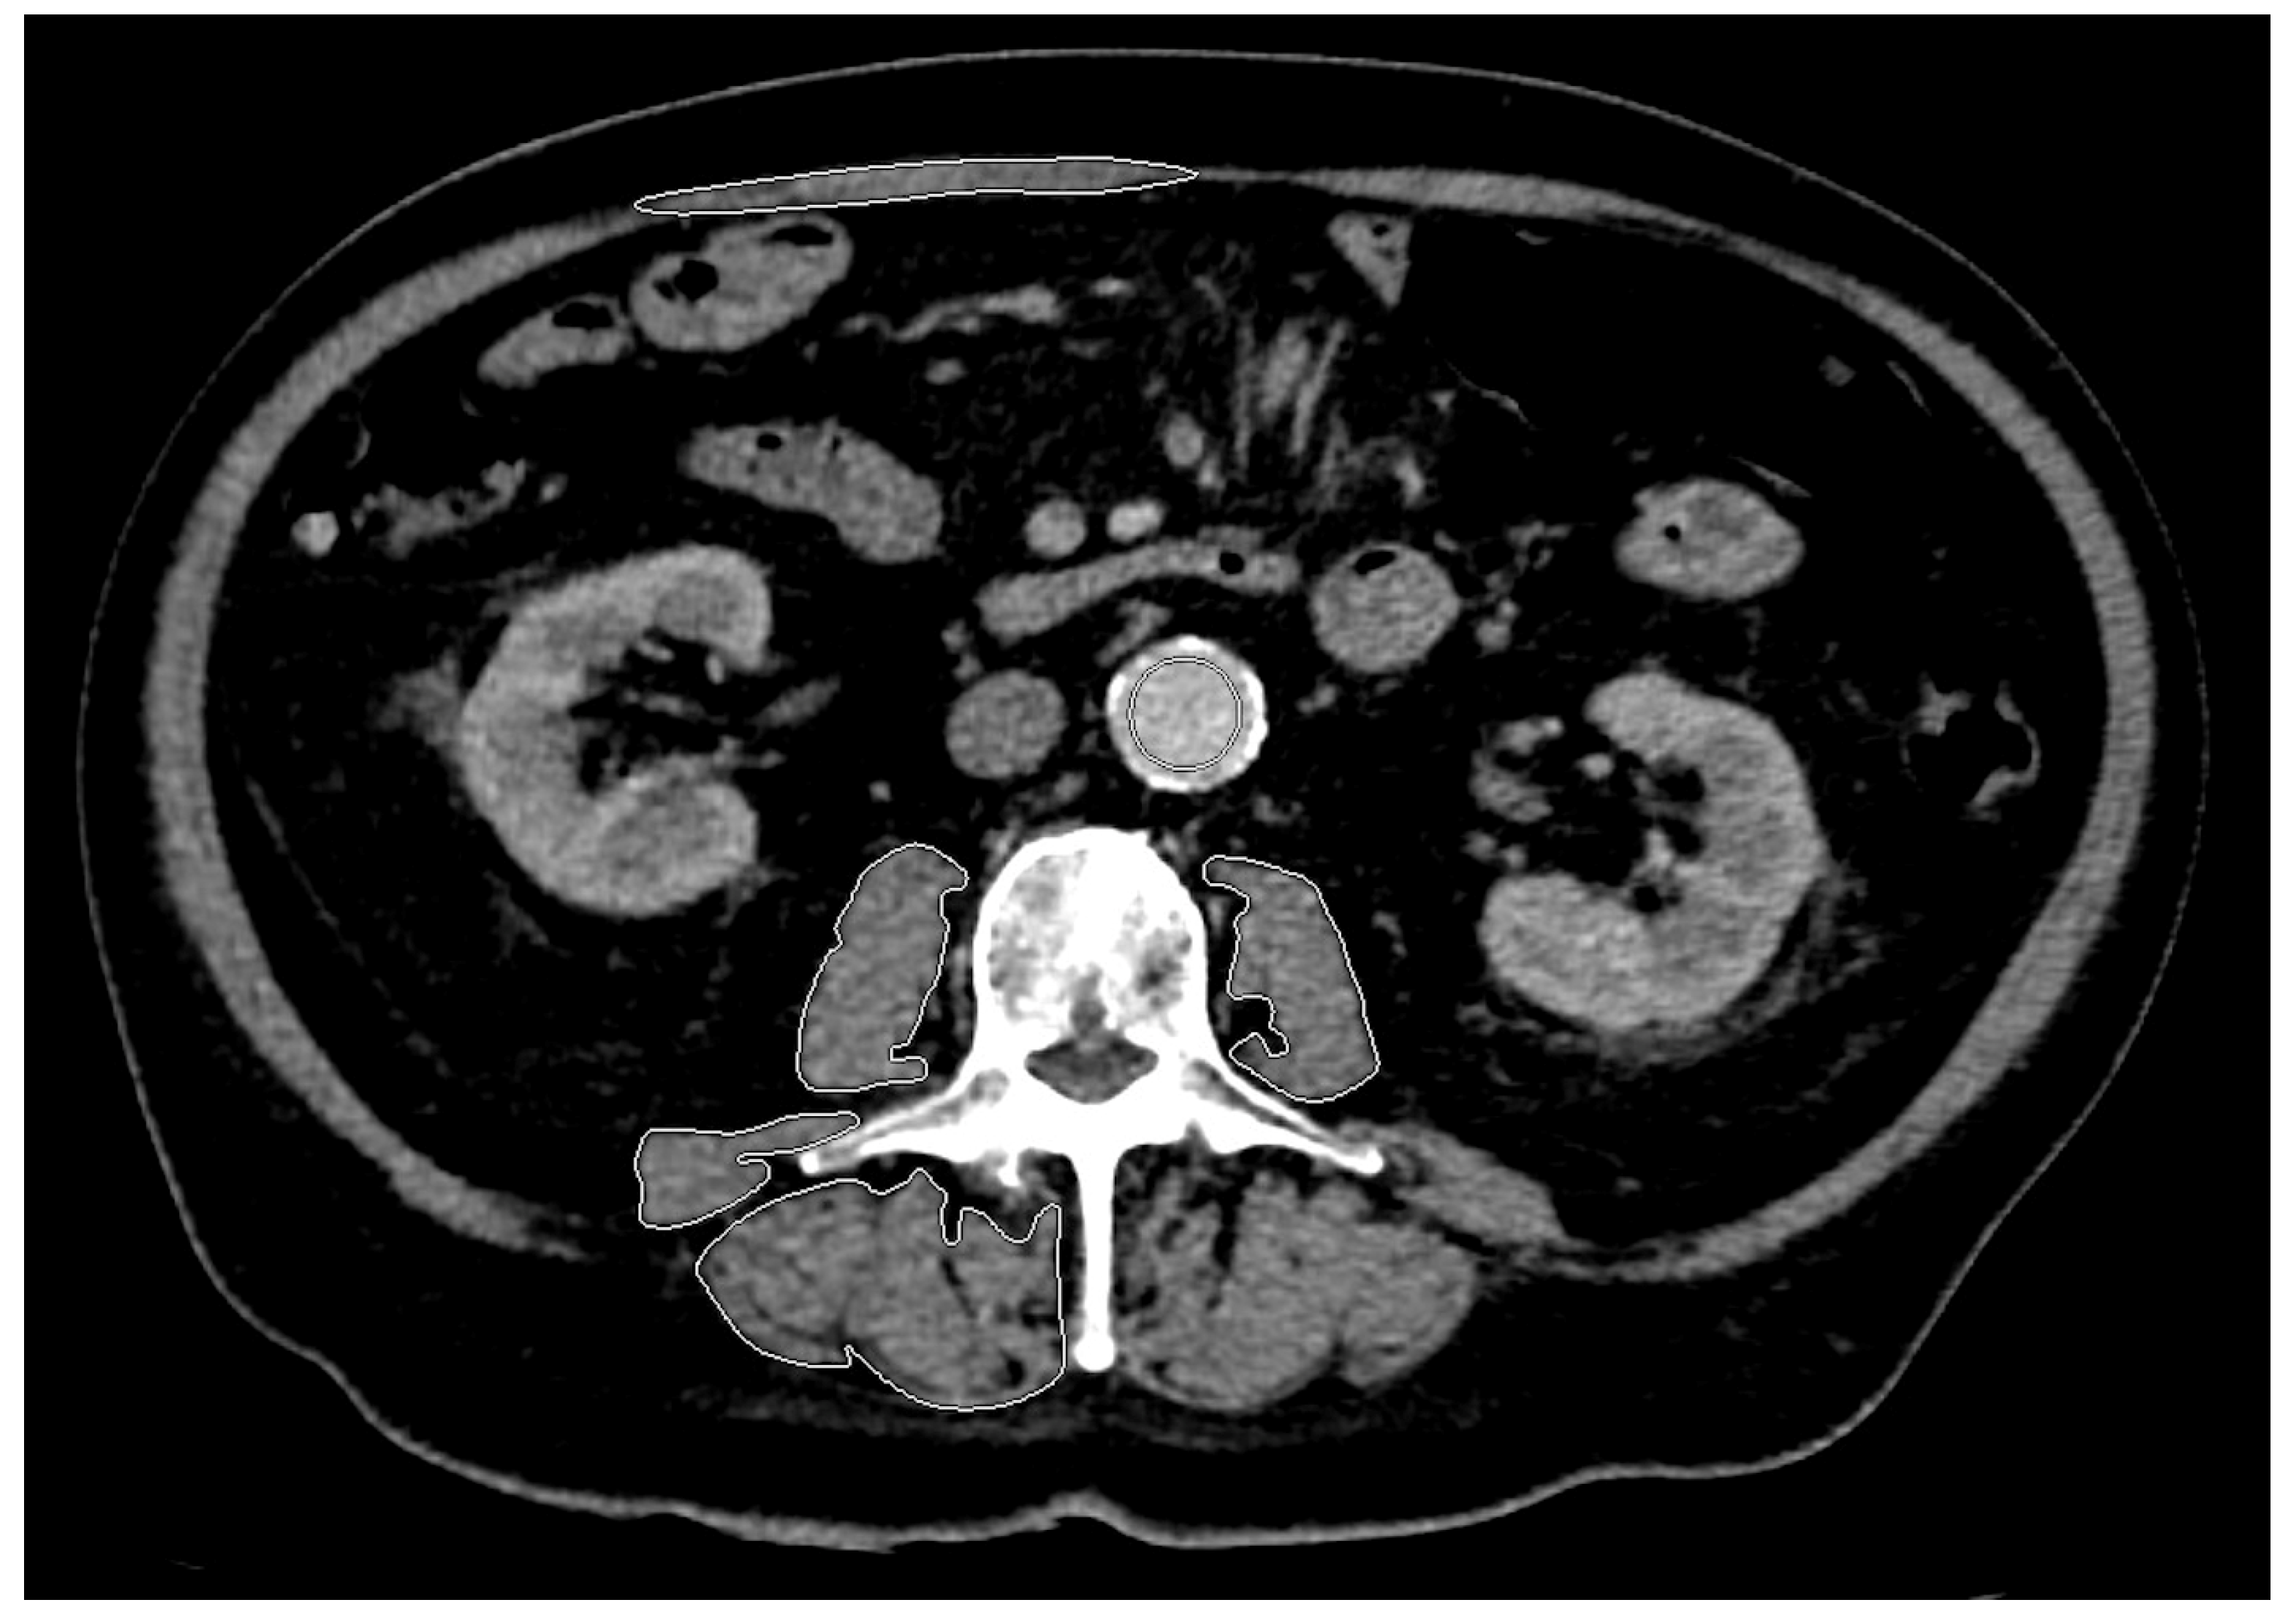

2.1. Muscle Segmentation and Assessment of Sarcopenia